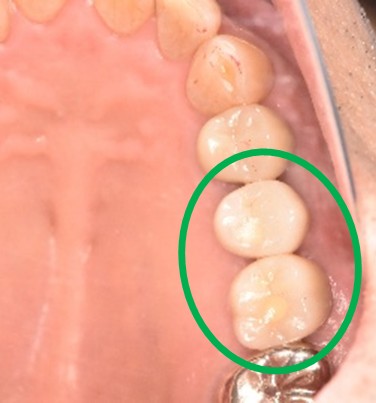

After